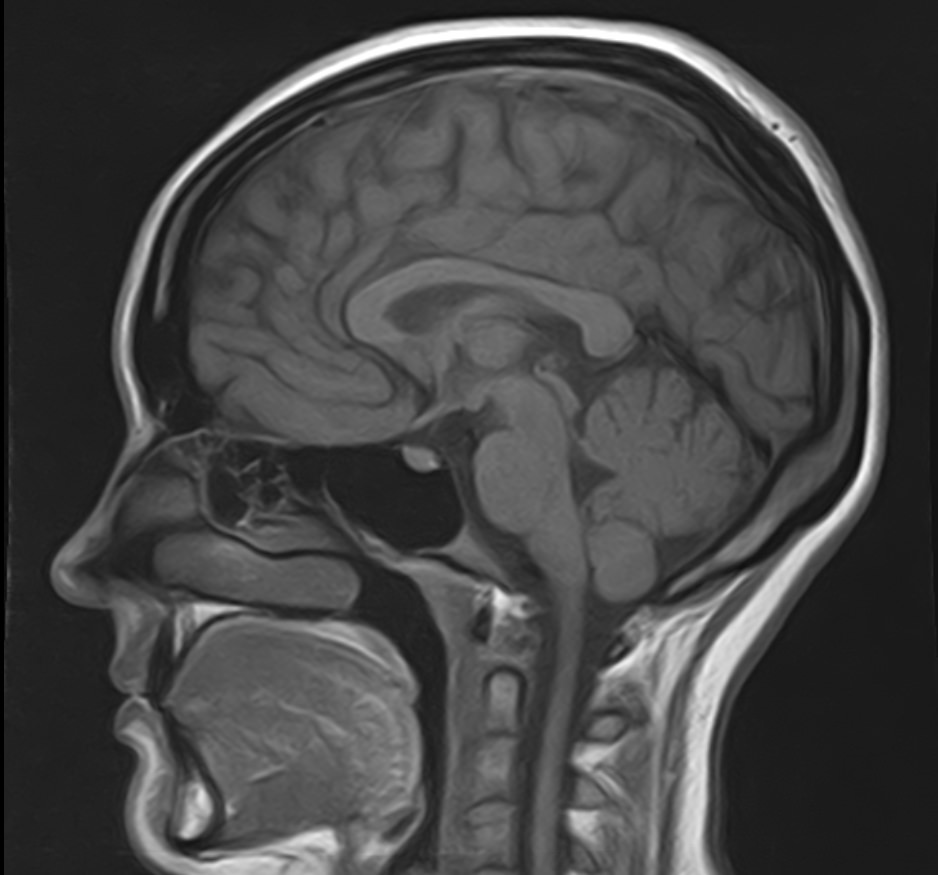

В клинике «Доступная медицина» можно пройти комплексное обследование, включающее в себя два протокола сканирования близко расположенных друг от друга анатомических областей – шейного отдела позвоночника и головного мозга.

Сканирование проводится на современном высокопольном магнитно-резонансном томографе закрытого типа TOSHIBA VANTAGE TITAN 1,5 Тесла, который делает послойные срезы в разных плоскостях с шагом от 1 мм и на основе полученных данных создает трехмерные изображения превосходного качества. Метод исследования позволяет в мельчайших подробностях визуализировать состояние всех структур головного мозга и шейного отдела позвоночника, что дает возможность выявлять патологические изменения на ранних стадиях и назначать своевременное лечение.